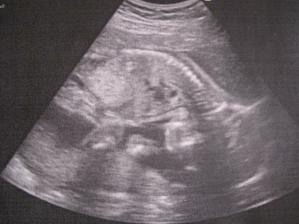

23.2. 2011 Byli jsme na velkém UTZ, ukázala se nám krásná zdravá holčička a pěkně čiperná 🙂